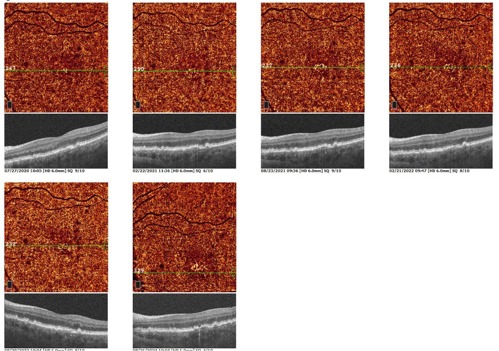

OCT and OCT-A were performed (Optovue Solix) to evaluate for signs of exudation OU and to assess the stability of her NE-MNV OS. No evidence of exudation or neovascularization was noted OD. OS showed stable drusen and a shallow retinal pigment epithelial detachment. OCT-A confirmed non-exudative CNV, slightly larger than previously noted. Of note, this was her first image on the Optovue Solix device. There was no evidence of intraretinal or subretinal fluid OS (Figures 5-7).

This case demonstrates that NE-MNV may stay relatively stable for years. There is speculation that this may be a protective mechanism to reduce risk of geographic atrophy. When a new non-exudative lesion is detected, the follow-up interval should be decreased with more frequent examination and imaging. With chronic lesions, patients can be typically monitored every 4 to 6 months.